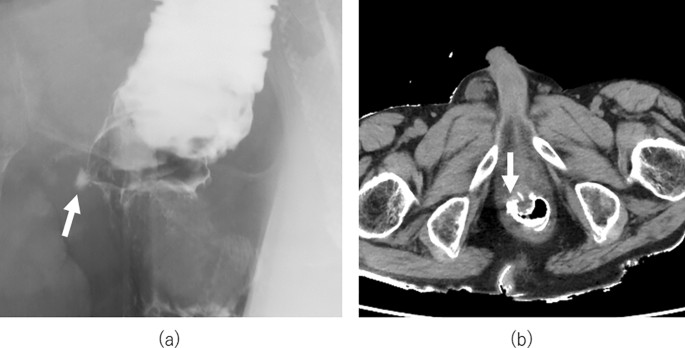

All 13 patients underwent contrast enema and plain CT examinations (median: 8 days after LAR, range: 6–13 days); in five patients, anastomotic leakage was suspected (Fig. 2a and Fig. 2b). In one of the patients with suspected anastomotic leakage, fever occurred after examination and required further treatment by changing the drainage tube (Clavien–Dindo (CD) classification III complication, Table 2). Early stoma closure was postponed due to ileus in one case, which was treated conservatively. Therefore, stoma closure within 2 weeks was performed in seven patients (53.8%).